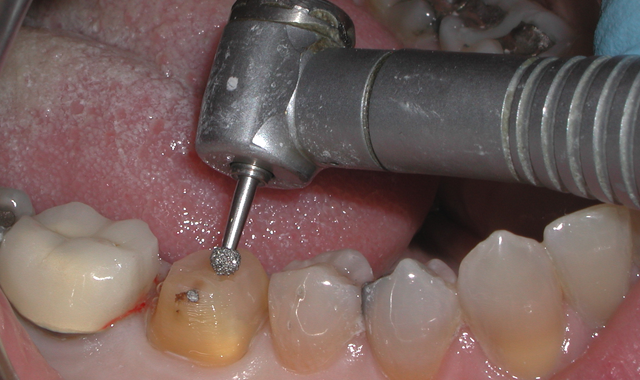

Fig. 2 Fig. 3

The chamber was then filled using CompCore™ AF (Premier Dental). CompCore AF is a dual-cured, fluoride-releasing, radiopaque composite core buildup indicated for vital and nonvital teeth (Figs. 3-4).